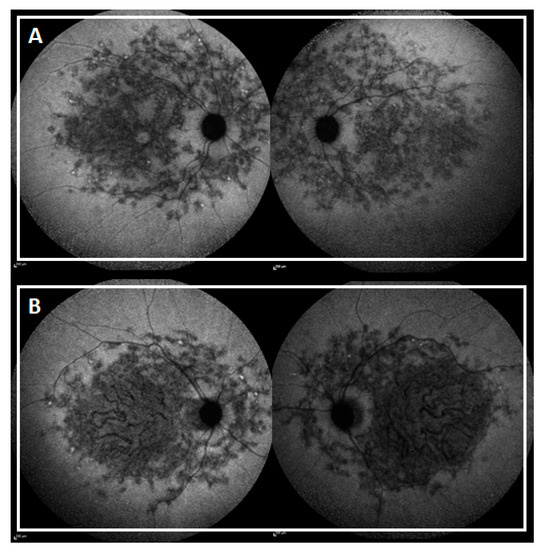

| SW-AF and NIR-AF | Group 1 | Central lesion with jagged border | Duncker et al., 2014 [55] |

| Group 2 | Lesion with extensive fundus changes | ||

| Group 3 | Central lesion with smooth border and hyperautofluorescent SW-AF and NIR-AF ring | ||

| Group 4 | Central lesion with smooth border and no hyperautofluorescent NIR-AF ring | ||

| Group 5 | Discrete central lesions better visualized in NIR-AF images | ||

| Peripapillary area preserved | No alterations within an eccentricity of 0.6 mm from the optic disc | Cideciyan et al., 2005 [56] | |

| Flecks in the peripapillary area | Presence of flecks within an eccentricity of 0.6 mm from the optic disc | ||

| Peripapillary area not preserved | Absence of EZ band and/or EPR atrophy within an eccentricity of 0.6 mm from the optic disc | ||